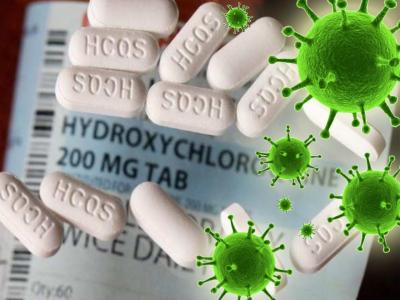

संपूर्ण जग सध्या कोरोना व्हायरसच्या संकटामुळे चिंतेत आहे. कोरोना व्हायरसवर अद्याप कोणतंही औषध उपलब्ध झालेलं नाही.

कोरोनावरील उपचार करण्यात हायड्रोक्सीक्लोरोक्वीन गोळ्या अत्यंत महत्त्वाच्या मानल्या जातात.

कोरोनाशी लढण्यासाठी ज्या देशांना हायड्रोक्सीक्लोरोक्वीन गोळ्यांची आवश्यकता असेल त्यांच्या मागण्यांची पूर्तता केली जाईल असे संकेत केंद्र सरकारने दिले आहेत. त्यामुळे या गोळ्या तयार करणाऱ्या कंपन्यांनीही निर्मिती कित्येक पटीने वाढवण्याचा निर्णय घेतला आहे.